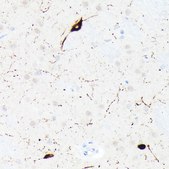

Anti-SST Antibody

rabbit monoclonal, 7Q4T0

Anti-Somatostatin (SST) Antibody, clone 7Q4T0, Rabbit Monoclonal,

immunohistochemistry: 1:50 - 1:200

General description

Recombinant fusion protein containing a sequence corresponding to amino acids 23-116 of human Somatostatin (SST) (NP_001039.1).

IHC